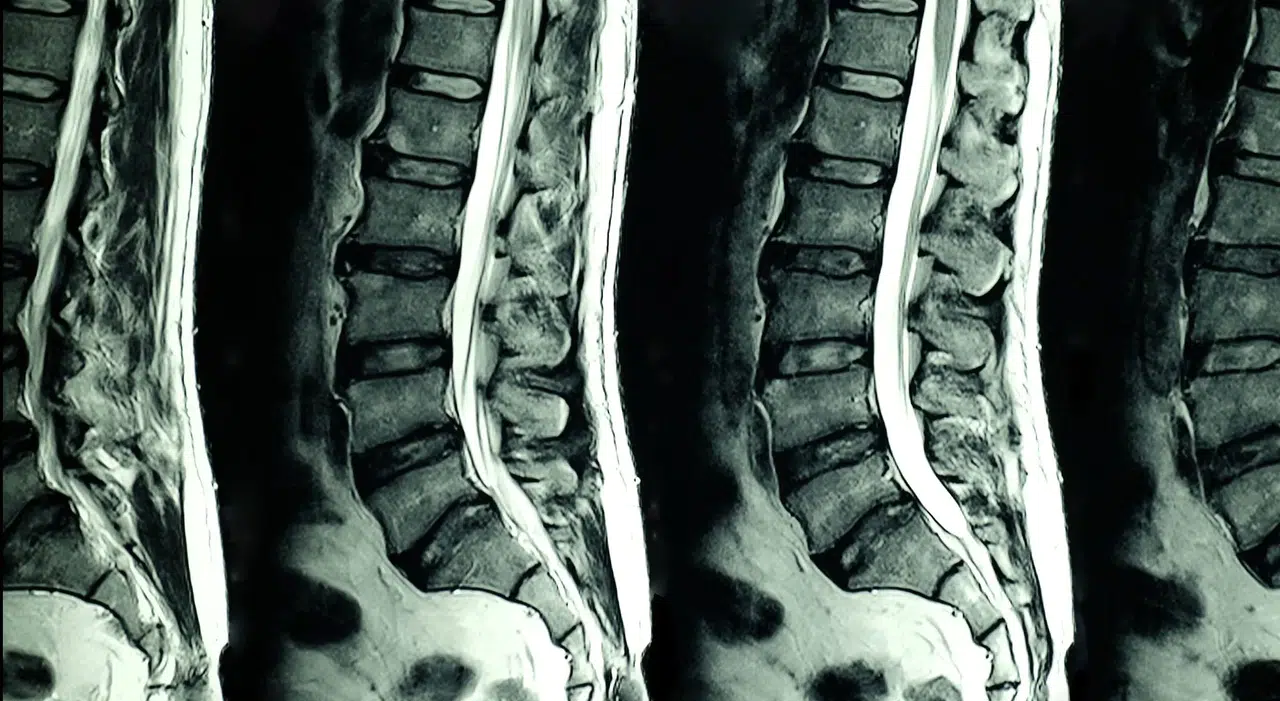

Tıpta intensite ne demek?

Tıp alanında intensite, özellikle MR (emar) ve BT görüntüleme raporlarında kullanılan bir terimdir. Bu bağlamda intensite, dokuların görüntüdeki parlaklık seviyesini ifade eder.

Hiperintens ne demek?

• Normalden daha parlak veya beyaz görünen alanları ifade eder

• Genellikle ödem, iltihap veya bazı patolojik durumlarla ilişkilidir

Hipointens ne demek?

• Normalden daha koyu veya siyah görünen bölgeler için kullanılır

• Farklı doku yoğunluklarını veya bazı hastalıkları gösterebilir

İzointens ne demek?

• Çevre dokularla aynı parlaklıkta görünen alanları ifade eder

• Genellikle normal ya da benzer yapıdaki dokular için kullanılır